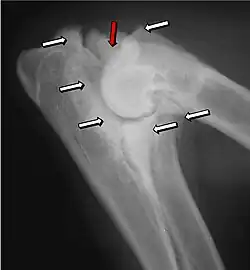

Isolierter Processus anconaeus (IPA)

Ein selbstständiger (isolierter) Ellenbogenfortsatz der Elle ist eine erblich bedingte Störung der enchondralen Ossifikation und wurde 1956 erstmals beschrieben. Beim IPA unterbleibt die Fusion zwischen Elle und ihrem Processus anconaeus, der ein eigenes Ossifikationszentrum besitzt, welches normalerweise im Alter von 18 bis 24 Wochen mit der Elle verschmilzt.[6] In diesem Alter besteht aufgrund einer verminderten Elastizität die Gefahr eines teilweisen oder vollständigen Abrisses durch ein Trauma oder das Ausbleiben des Fugenschlusses infolge hoher körperlicher Aktivität. Als weitere Ursache wird ein vermindertes Längenwachstum der Elle (sog. short-ulna-syndrome) diskutiert. Eine Überversorgung mit Calcium und Phosphor begünstigt das Auftreten eines IPA.[14] Überdurchschnittlich betroffen sind Rottweiler und Deutscher Schäferhund. Bei Rüden ist die Erkrankung häufiger als bei Hündinnen. In etwa 60 % der Fälle tritt ein IPA einseitig auf.

Die Diagnose wird anhand eines Röntgenbildes in Beugestellung des Gelenks gestellt, wobei zu beachten ist, dass der Processus anconeus erst mit etwa sechs Monaten mit der Elle verschmilzt. Die Frakturlinie ist in den meisten Fällen gut sichtbar, außerdem kommt es zu Sklerosierungen des betroffenen Bereiches und bei längerem Bestehen zu Knochenanbauten.